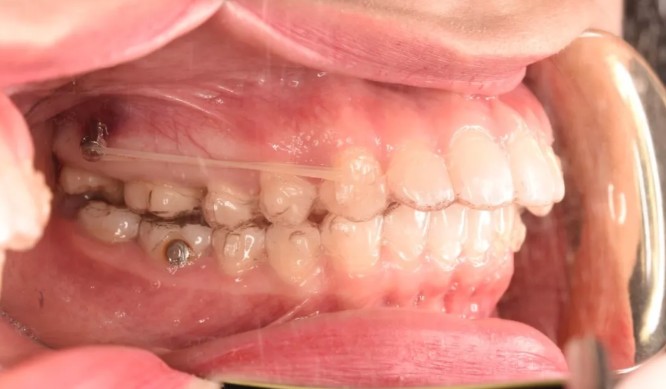

妹紙做隱適美磨牙后推打骨釘?shù)恼澜?jīng)歷,沒(méi)想到效果挺不錯(cuò)

隱適美牙博士口腔隱形矯正牙齒發(fā)布時(shí)間: 2020-02-12

為了不拔牙,我選擇了在溫州牙博士口腔做隱適美磨牙后推打支抗釘矯正,沒(méi)想到真如醫(yī)生所說(shuō),效果挺不錯(cuò)的!來(lái)說(shuō)說(shuō)我的整牙經(jīng)歷吧~